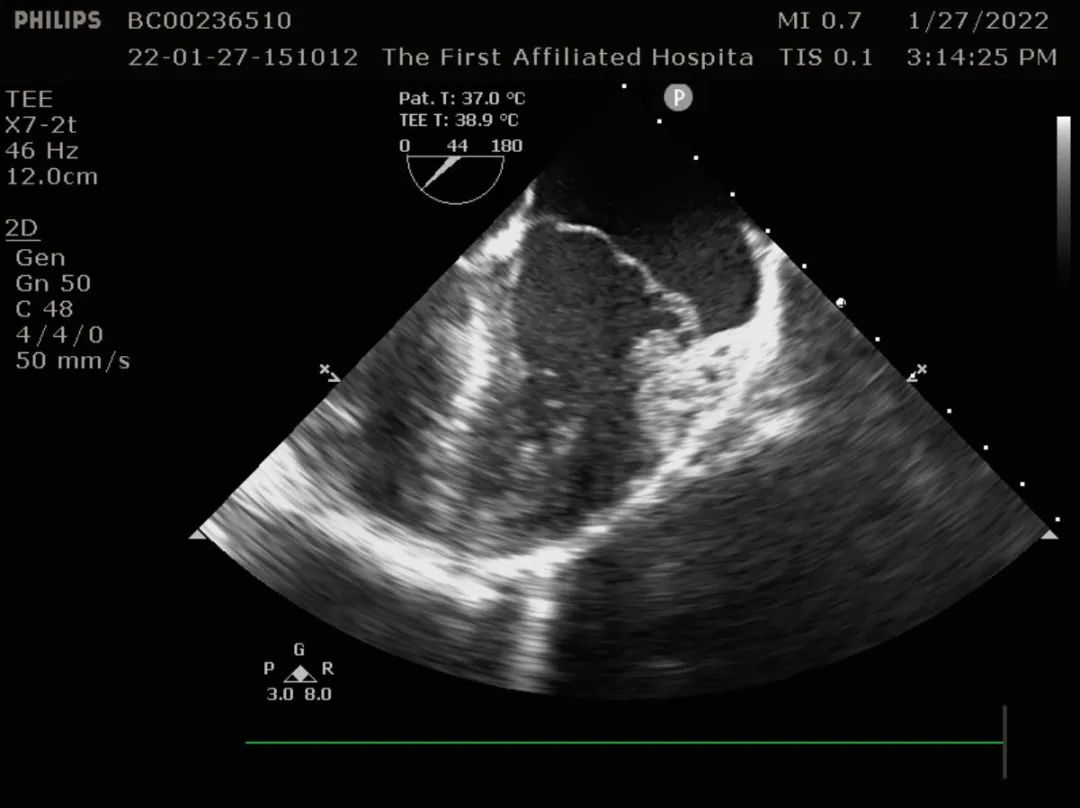

二尖瓣后叶脱垂,大量返流

术中食道超声提示二尖瓣瓣叶冗长,组织增厚,多处返流。提示barlow综合征可能。

术中探查二尖瓣叶过长,瓣叶过长部分常稍增厚、起皱,呈苍白色。术中盐水注水检查发现P2、A2、P3、C2区多处返流。证实患者为barlow综合征。

术中食道超声监测